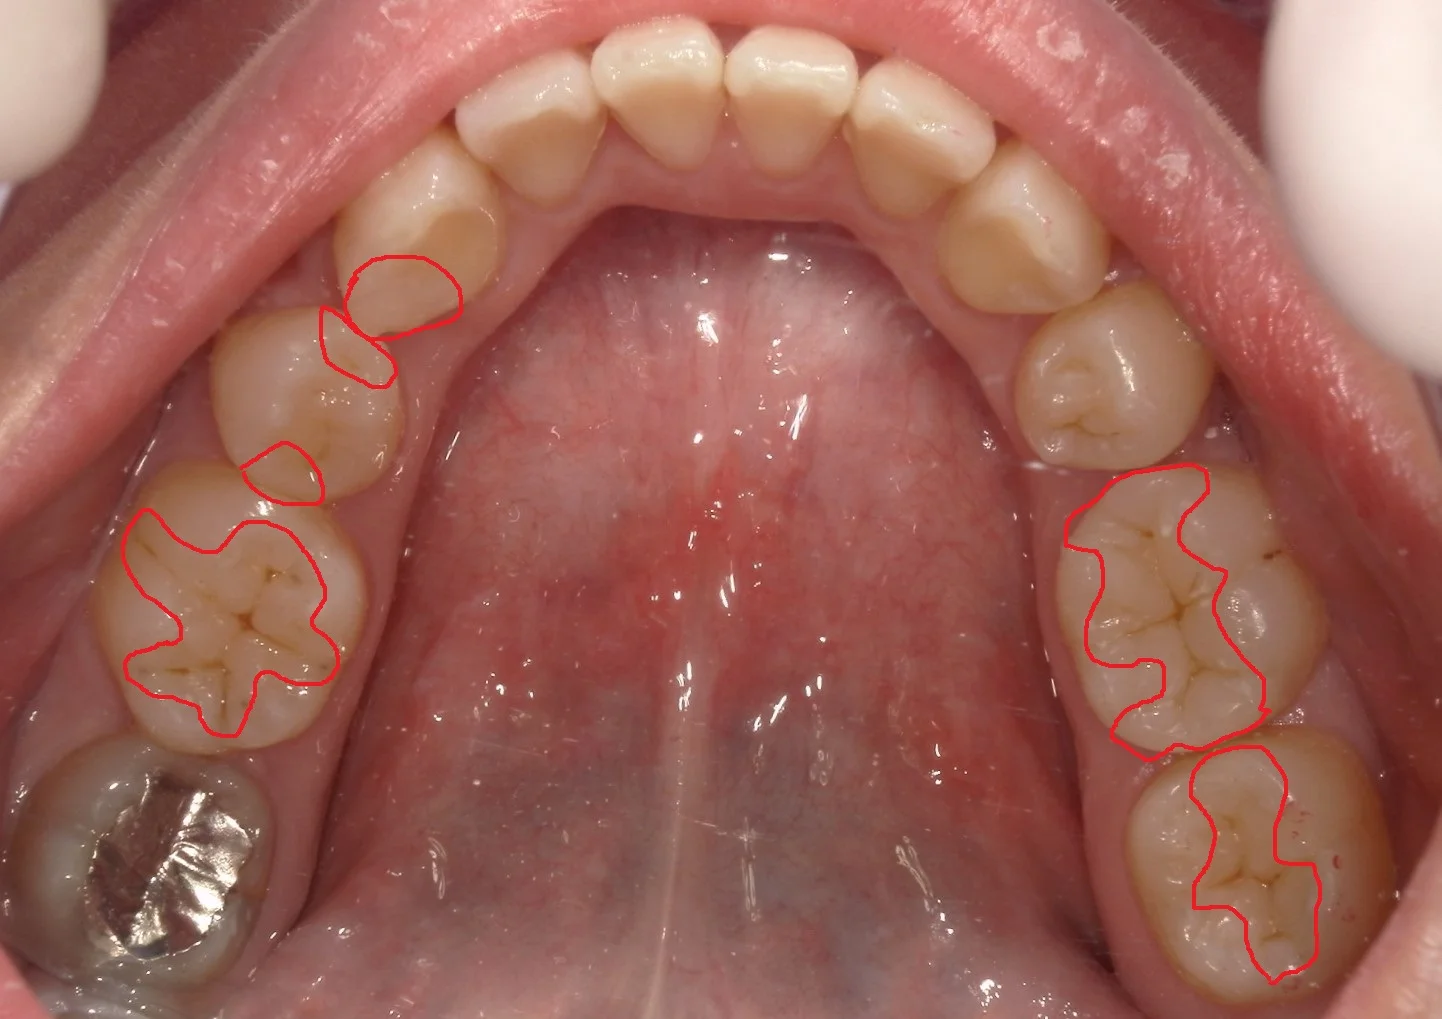

さて、この上下の歯のどこをどこを治療したでしょうか・・・!!

正解は下の方で・・・!

正解はこんな感じですヽ(゚∀゚)ノ パッ☆

計4回で治療終了まで行きました!